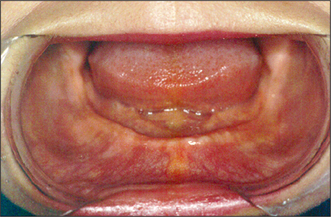

image

Fig. 11.31 A healing abutment is placed to ensure good healing of oral mucosa to the surface of the abutment.